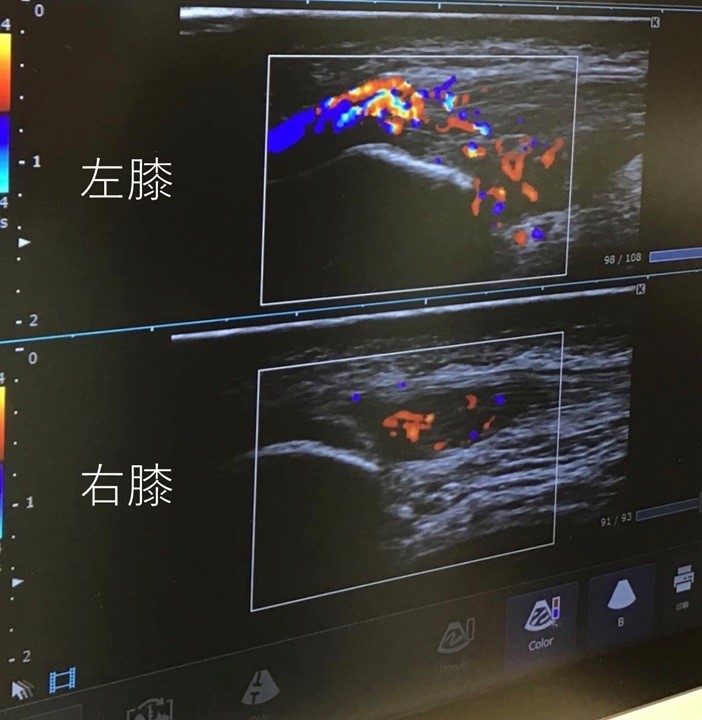

エコーで膝の状態を見ると、痛みを起こす異常な血管(モヤモヤ血管)が両膝の膝蓋腱にできていることがわかりました。(下の図)

特に左膝の炎症が強く、膝蓋腱の全層にわたってモヤモヤ血管が生じており、「これほど重症であると、体外衝撃波やPRP注射では太刀打ちできないだろうな」という印象でした。